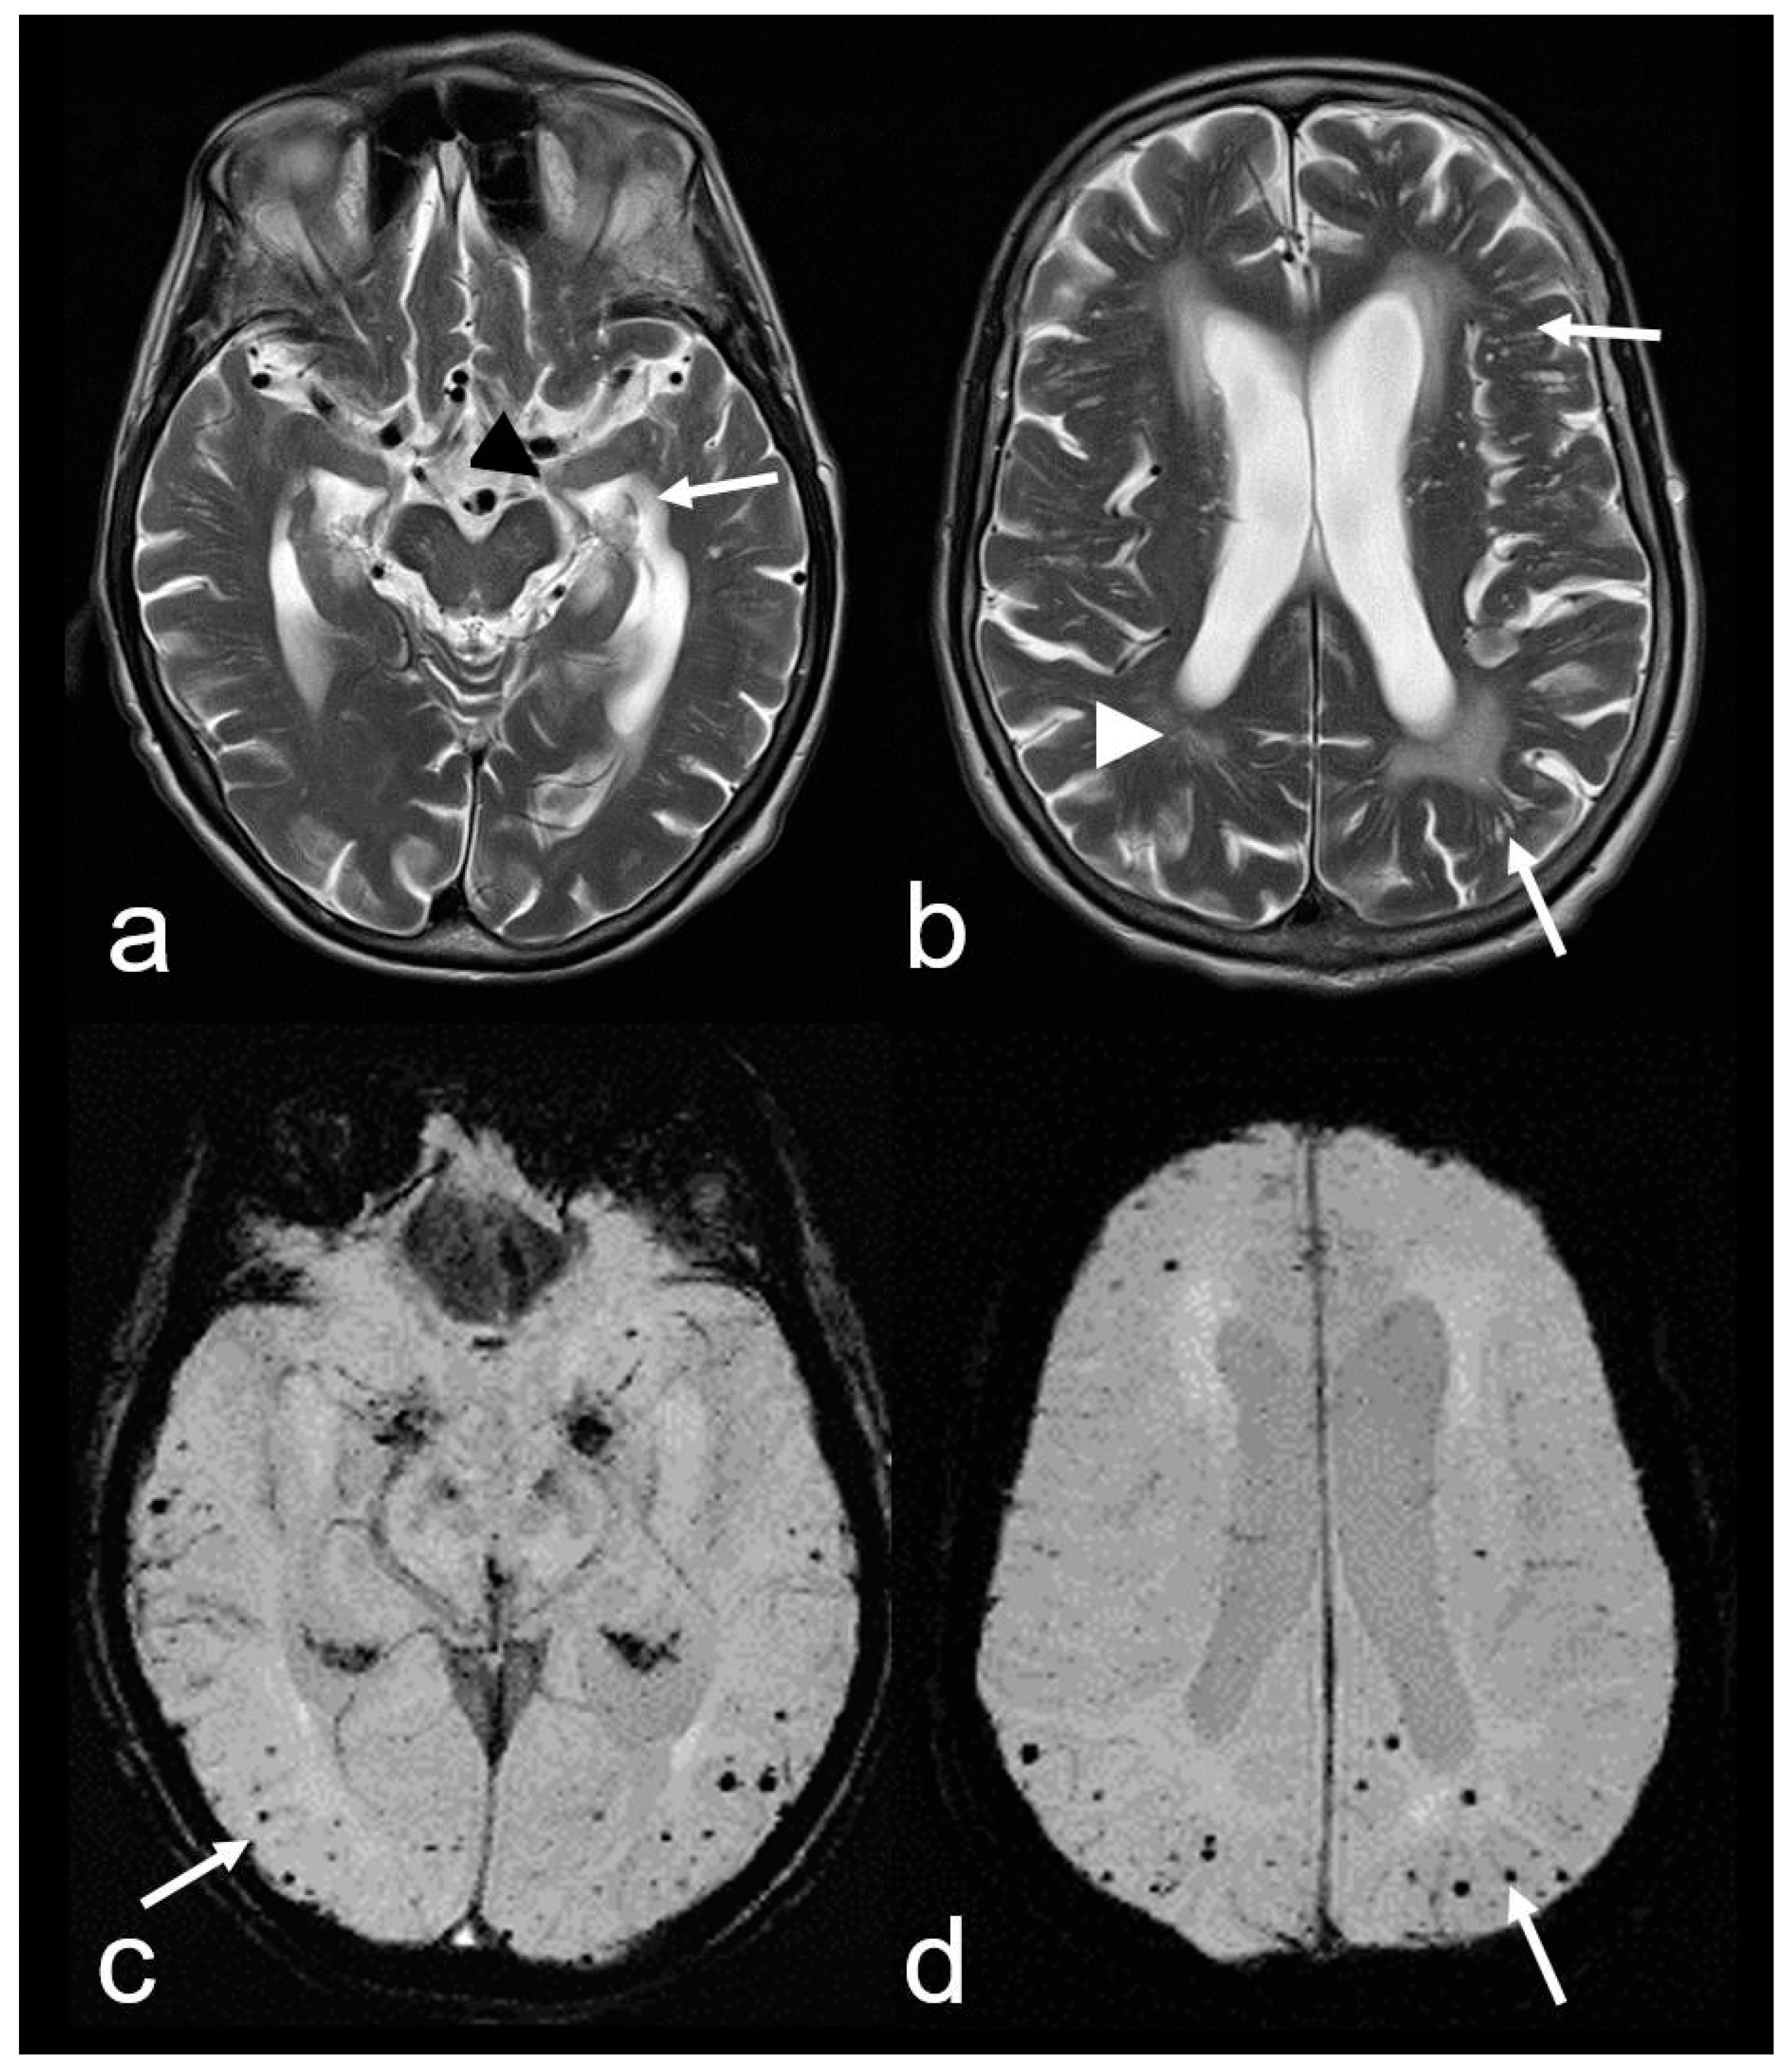

Figure 4.

A 74-year-old man with progressive cognitive impairment suffering from temporary sensory–motoric deficits right. Cortical subarachnoid hemorrhage (cSAH) in the central sulcus ((a), CT: arrow; Siemens Somatom Emotion). MRI with sulcal hyperintense signal changes on fluid attenuated inversion recovery (FLAIR) images ((b), arrow), sulcal signal loss on susceptibility-weighted imaging (SWI, (c): arrow), additional multifocal cortical superficial siderosis (cSS) bilateral ((c–e), arrowhead); note the characteristic bilinear track-line appearance of cSS in the chronic stage ((c), arrowhead); (d,e): multiple cortical/subcortical microbleeds (MB, arrow); (f): SWI-phase image demonstrating paramagnetic effects in the central sulcus due to blood degeneration products (arrow); MRI 1.5 T Siemens AREA.

3. Cortical SAH (cSAH) is frequently localized in the frontodorsal and central regions over the convexity near the vertex [43,44,45,46] (Figure 4). CAA is, by far, the most frequent cause of cSAH, especially in older individuals, and may occur repeatedly at different locations (see Figure 4) [46,62,63]. However, the etiology of cSAH also includes peripheral aneurysms, arteriovenous malformation (AVM), dural fistula, reversible cerebral vasoconstriction syndrome (RCVS) and tumors or preceding high-grade arterial stenosis, vasculitis and venous outflow obstruction [45,46,62,64]. Therefore, comprehensive clinical and neuroradiological assessments are essential. Clinical signs are often TFNE (‘amyloid spells’) [1,33,34,35,36]. The patients typically experience multiple episodes of contralateral sensory disturbances, each lasting approximately 15 min, often occurring within a 24 h period [33,34]. From a neurological perspective, differential diagnosis in an emergency setting can be challenging, as it may be difficult distinguish these episodes from TIAs or focal epileptic seizures, such as sensory Jackson seizures [36].

4. Cortical superficial siderosis (cSS) refers to the presence of linear hemosiderin in the leptomeninges and the superficial layers of the cerebral cortex, most commonly as a sequela of a previous acute cSAH [62,65,66,67,68,69,70]. It is important to differentiate between localized cSS, which affects 1–3 sulci, and disseminated cSS, which affects at least 4 sulci [70]. In the acute stage, T2*-weighted imaging (WI) and susceptibility-weighted imaging (SWI) typically show homogeneous signal loss, while in the chronic stage, a bilinear, “track-line” appearance is characteristic (Figure 4) [63,65,66].